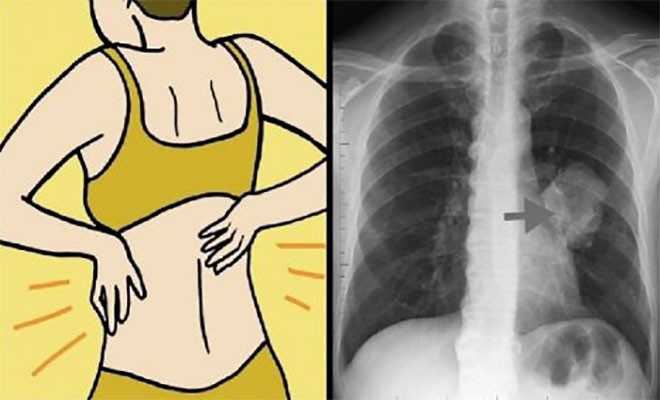

Σημάδι # 1: Δυσκολία στην αναπνοή

Οι περισσότεροι από εμάς δυσκολευόμαστε ν’ αναπνεύσουμε μετά την άσκηση. Αν με το που σηκωθείτε από το κρεβάτι δυσκολεύεστε ν’ αναπνεύσετε, τότε αυτό μπορεί να είναι μια σοβαρή ένδειξη αναπνευστικών προβλημάτων Η δύσπνοια είναι ένα από τα πρώτα συμπτώματα του καρκίνου του πνεύμονα.

Σημάδι # 3: Συνεχής βήχας

Αν έχετε επίμονο βήχα που όχι μόνο δεν φεύγει αλλά φαίνεται να χειροτερεύει, ήρθε η ώρα να πάτε για ένα τσεκάπ. Ο βήχας είναι η φυσική αντίδραση του σώματός μας σε έναν ερεθισμό στο αναπνευστικό μας σύστημα, αλλά επιμένει, σημαίνει ότι επιμένει κι ο ερεθισμός ή η αιτία που τον προκάλεσε. Ο επίμονος βήχας είναι ένα σημαντικό σημάδι έγκαιρης προειδοποίησης του καρκίνου του πνεύμονα, και μπορεί να σας βοηθήσει να εντοπίσετε το πρόβλημα και να αναζητήσετε γρήγορα θεραπεία.

Σημάδι # 4: Πόνος στους ώμους και στην πλάτη

Δεν θα σκεφτόσασταν ότι ο πόνος στην πλάτη σας θα συνδέονταν με τους πνεύμονές σας, αλλά για τις γυναίκες, οι απότομοι πόνοι και οι πόνοι στους ώμους μπορεί να δείχνουν ότι κάτι δεν πάει καλά. Αυτό συμβαίνει γιατί οι γυναίκες είναι πιο επιρρεπείς σε μια μορφή καρκίνου του πνεύμονα που ονομάζεται αδενοκαρκίνωμα. Οι όγκοι από αυτή τη μορφή καρκίνου αυξάνονται στα εξωτερικά στρώματα των πνευμόνων, έτσι μπορεί να ασκούν πίεση στην πλάτη και τη σπονδυλική στήλη.

Σημάδι# 8: Πόνος στο στήθος

Όπως σημειώσαμε νωρίτερα, τα αδενοκαρκινώματα έχουν μερικές φορές ελαφρώς διαφορετικά συμπτώματα από άλλες μορφές καρκίνου του πνεύμονα. Μπορούν να προκαλέσουν πόνο στο στήθος με τον ίδιο τρόπο που προκαλούν πόνο στην πλάτη. Εάν παρουσιάζετε επίμονο πόνο σε ένα σημείο στην πλάτη σας, ίσως ήρθε η ώρα για μια δεύτερη γνώμη.